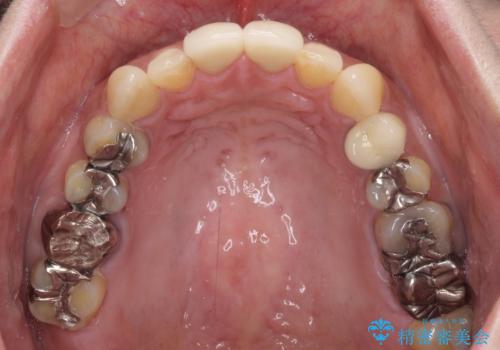

色彩や形態が大きく改善されたことはもちろん、虫歯によってしみていた症状もなくなり、患者様には大変満足していただきました。